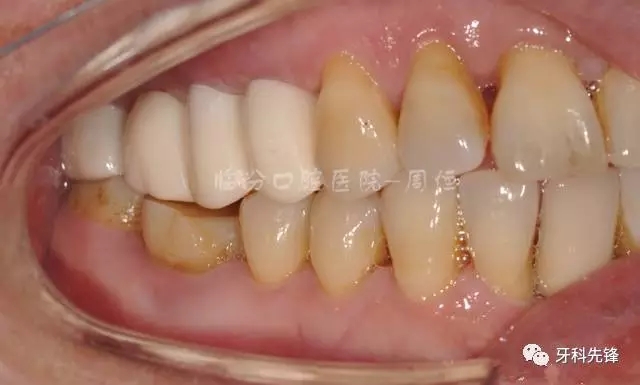

圖29術(shù)后頰面照

640.webp (33).jpg